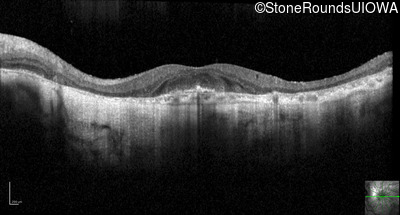

Optical Coherence Tomography - Left - 20/40 +1

Exemplar / OCT Stack

OCT Stack